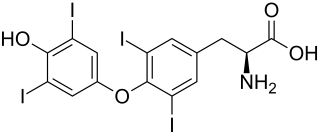

Die Radiojodtherapie (RJT, auch Radioiodtherapie, RIT) ist ein nuklearmedizinisches Therapieverfahren zur Behandlung der Schilddrüsenautonomie, des Morbus Basedow, der Schilddrüsenvergrößerung und bestimmter Formen des Schilddrüsenkrebses. Eingesetzt wird das radioaktive Jod-Isotop Jod-131, das ein überwiegender Beta-Strahler mit einer Halbwertszeit von acht Tagen ist und im menschlichen Körper nur in Schilddrüsenzellen gespeichert wird.

Das verwendete radioaktive Jod-Isotop Jod-131 steht als Natriumjodid in Kapselform und in wässriger Lösung zur Verfügung. Es wird in der Regel peroral verabreicht, kann in Ausnahmefällen (zum Beispiel bei ausgeprägten Schluckstörungen) auch intravenös appliziert werden. Bei peroraler Aufnahme wird das Jod rasch über die Magenschleimhaut aufgenommen und an das Blut abgegeben (Resorption). Über den Natrium-Jodid-Symporter gelangt das Jod in die Schilddrüsenzelle und wird letztlich im Schilddrüsenfollikel gespeichert. Unter der Wirkung von TSH oder TSH-Rezeptor-Autoantikörpern ist die Aufnahme von Jod in die Schilddrüsenzellen erhöht. Autonome Anteile der Schilddrüse nehmen Jod unabhängig vom TSH auf.

Jod-131 ist ein in Kernreaktoren hergestelltes Nuklid und hat eine Halbwertszeit von 8,02 Tagen. Bei seinem Zerfall zu stabilem Xenon wird ein Beta-Teilchen frei – mit der maximalen Energie von 0,61 MeV und einer mittleren Reichweite in Gewebe von 0,5 mm. Diese Strahlung ist für die therapeutische Wirkung verantwortlich. Darüber hinaus wird auch Gammastrahlung mit dem Hauptpeak bei 364 keV frei, die die Schilddrüse verlassen kann und daher einerseits für die unerwünschte Strahlenexposition des Patienten und der Umgebung verantwortlich ist, andererseits aber auch für die Bildgebung und den Radiojodtest verwendet werden kann.